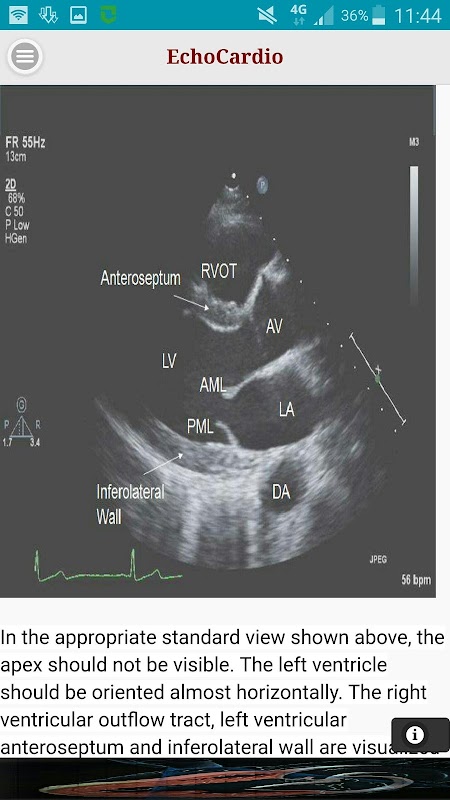

Parasternal Uzun Eksen